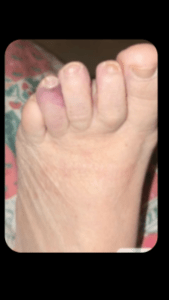

Ruolo della QMR Therapy nel trattamento del piede diabetico